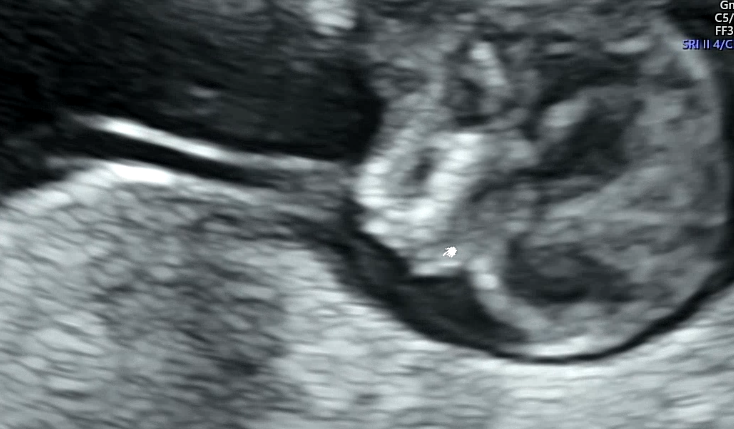

1차 기형아 검사의 포인트!

목투명대의 두께와 콧대의 유무이다.

태아가 너무 움직여서 심장소리와 목 투명대 길이를 재는데 애를 먹었다. 초음파를 보면서 귀엽다는 생각이 드는 나는 엄마가 되어가는 건가...!

목 투명대는 1.46mm가 나와서 정상이라고 하셨다. 1~3mm 사이면 정상 범위이고 3mm이상부터는 다운증후군 고위험군으로 판단된다. 그런데 2.5mm 대 정도도 걱정스러운 정도라서 좀 더 정확한 검사인 니프티 검사를 해보자고 하기도 한다.

콧대가 없으면 안면장애나 다운증후군이 의심되는데 콧대도 발견되었다!